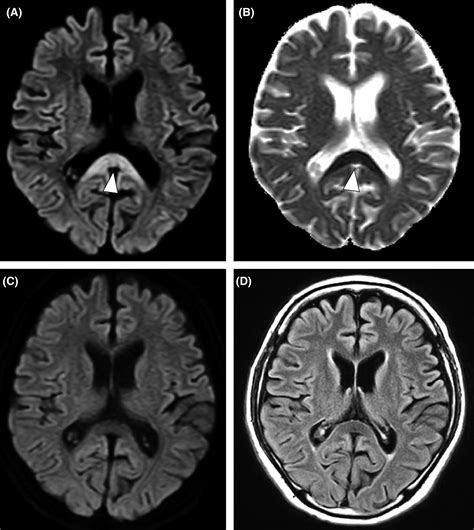

Due to its high concentration of neural pathways, the splenium of corpus callosum is a frequent area of interest in neuroradiology. Magnetic Resonance Imaging (MRI) is the gold standard for evaluating this region. Changes in the integrity of the splenium can be a marker for a variety of neurological conditions, ranging from developmental disorders to acute inflammatory processes.

When clinicians observe signal abnormalities in the splenium, they often look for what is termed "reversible splenial lesion syndrome" (RESLES). This condition often presents with acute onset of symptoms such as confusion, seizures, or vision changes, but interestingly, the lesions often resolve over time without permanent damage. This highlights the unique vulnerability and resiliency of the splenium to metabolic and inflammatory stressors.